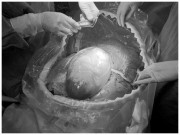

Đến tuần thứ 36, ba bé đã chào đời khỏe mạnh, với cân nặng lần lượt là 2350 gram, 2450 gram và 2500 gram. Ca phẫu thuật được thực hiện bởi Ths.BSCKII Trần Ngọc Đính - Trưởng khoa Tự nguyện D5 - và ekip đã diễn ra thuận lợi, mẹ tròn con vuông.

Ca sinh diễn ra thành công với sự khéo léo và cẩn thận, chuyên môn cao của đội ngũ y bác sĩ.